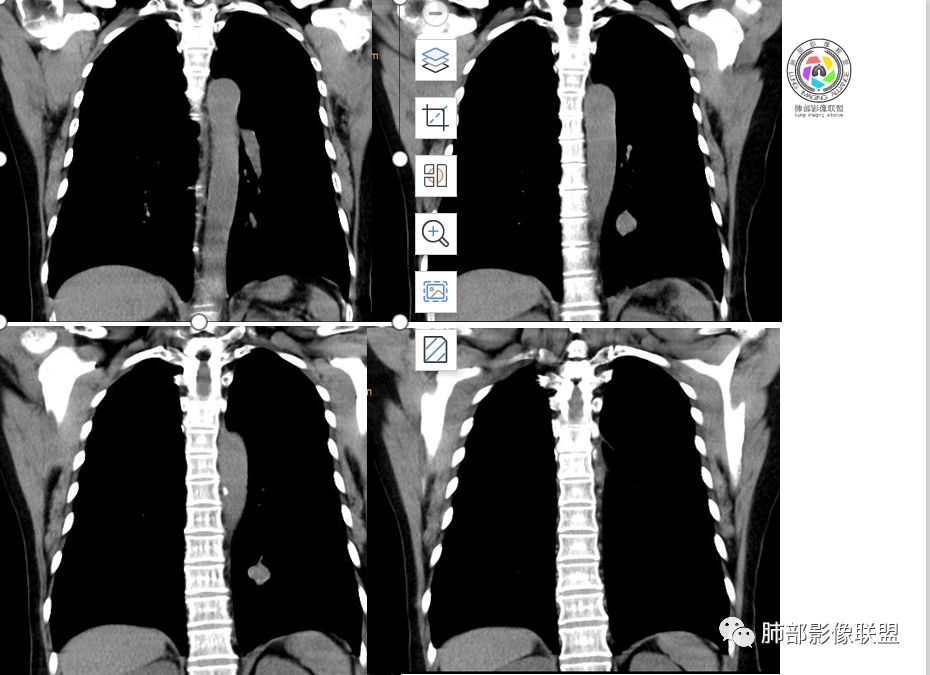

崔刚:当时写报告看好像是支气管确实没堵,受压的改变。

横断位应该显示了这个支气管,当时记得特意考下来图了

Shelia:隆突下没看到肿大淋巴结呀南边:那就是支气管应该是堵了。图少了一点

1.图片未能提供病灶与支气管的确切关系,支气管截断有助于大细胞癌或腺癌的判断,管腔狭窄有助于小细胞癌的判断。